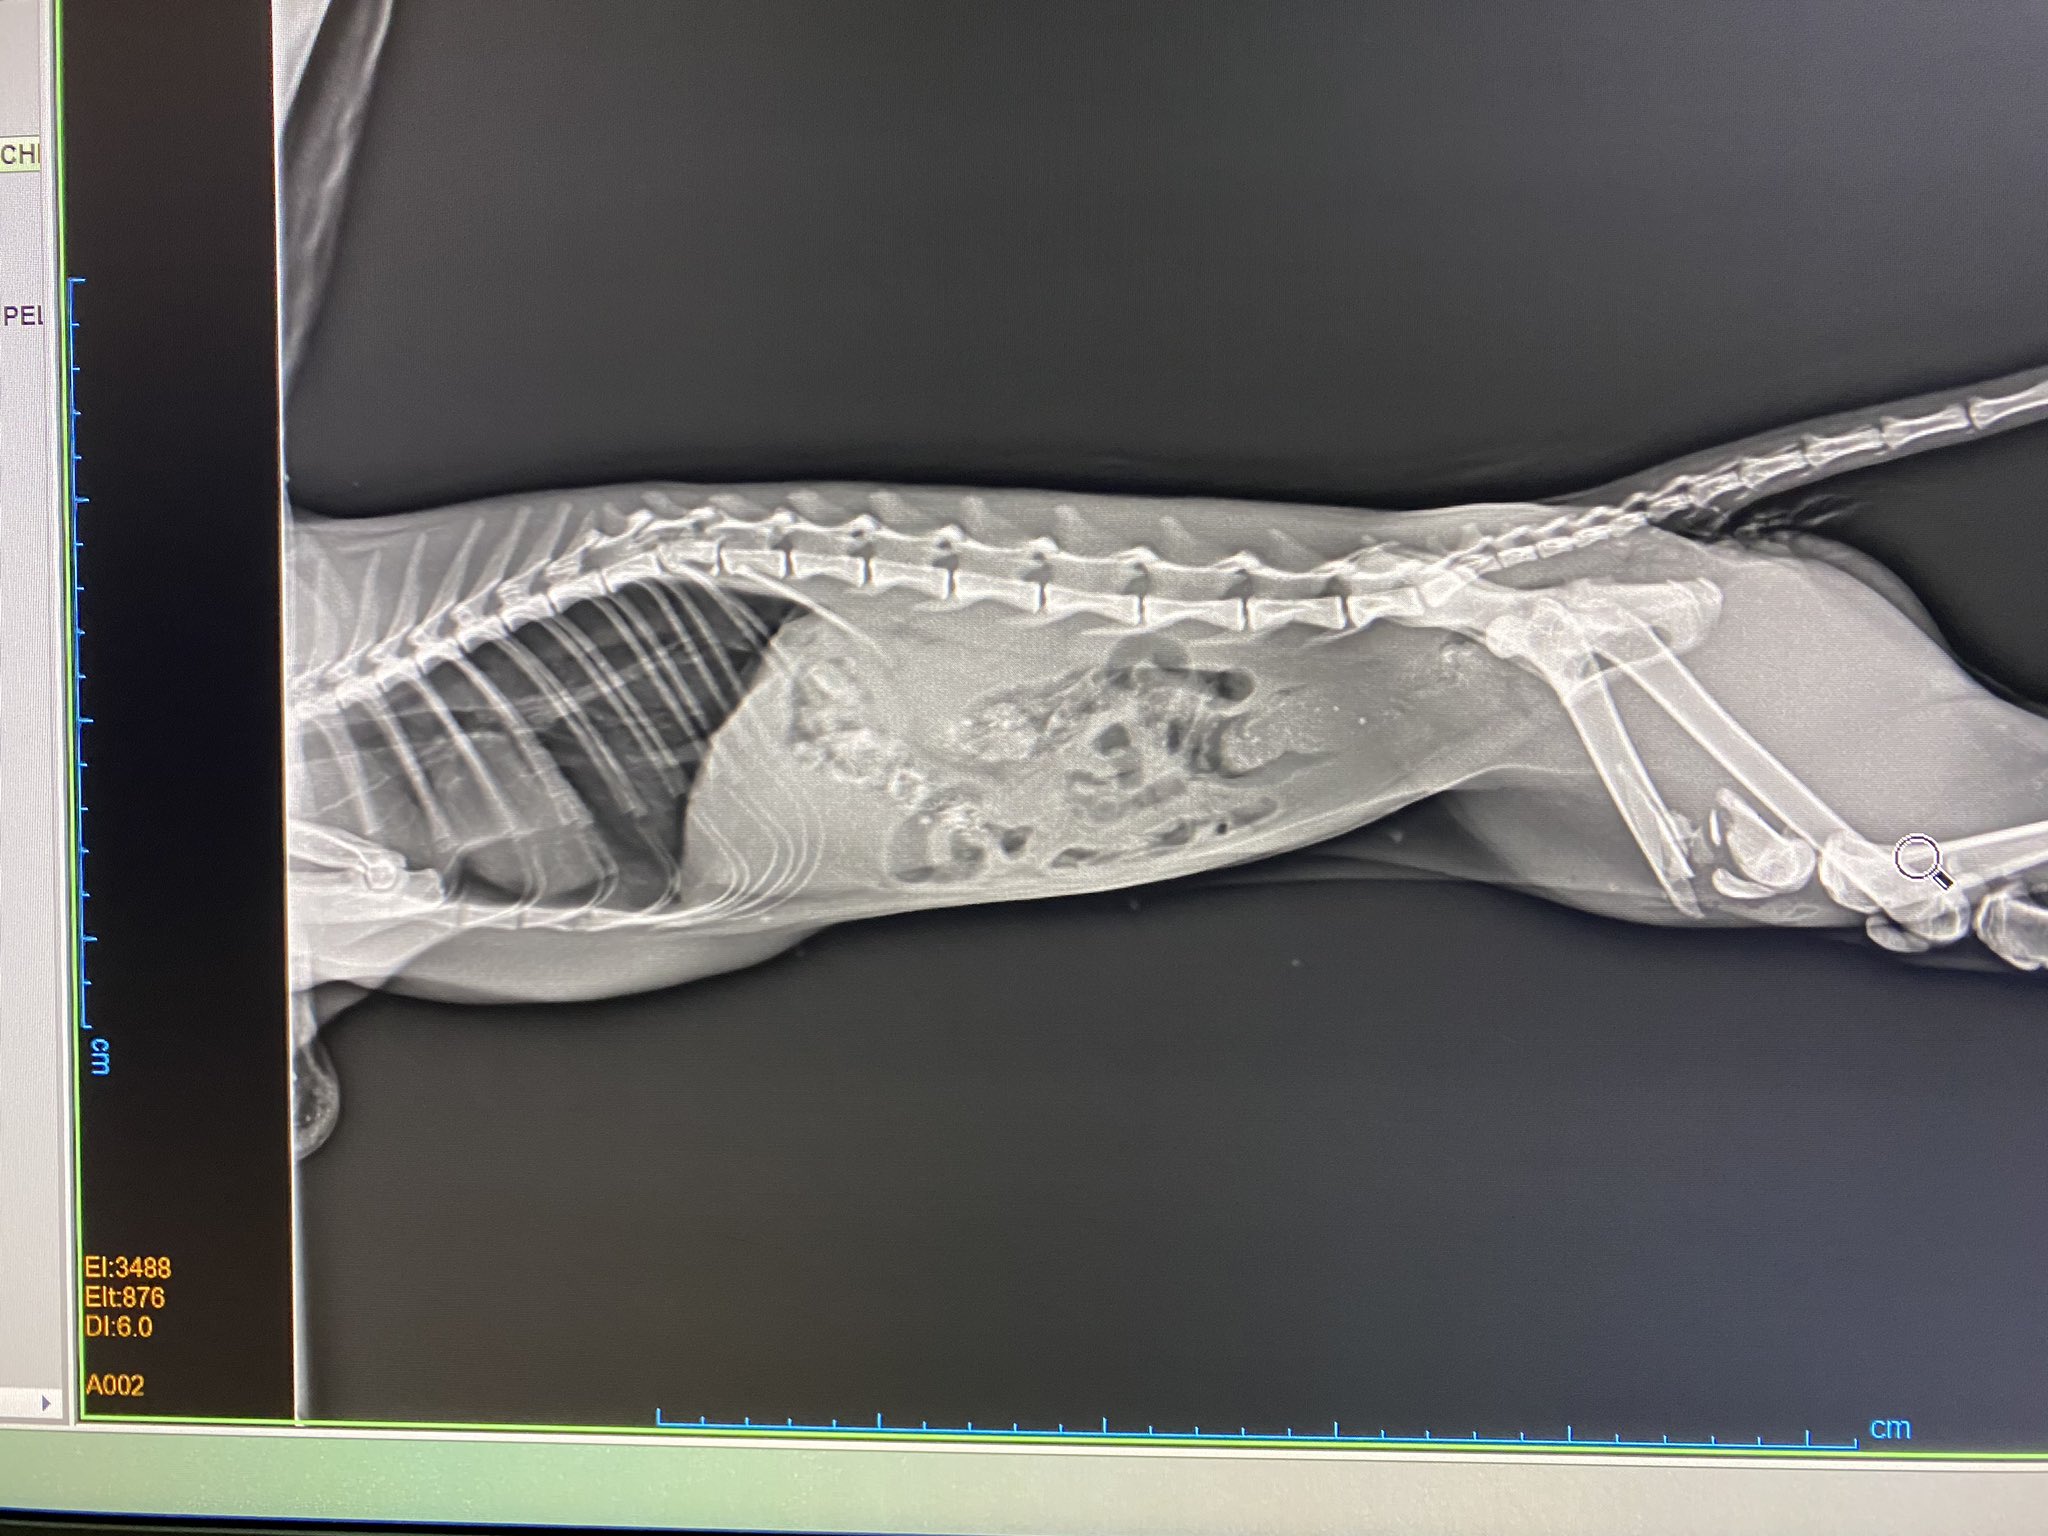

Kedilerde Kalça Çıkığı